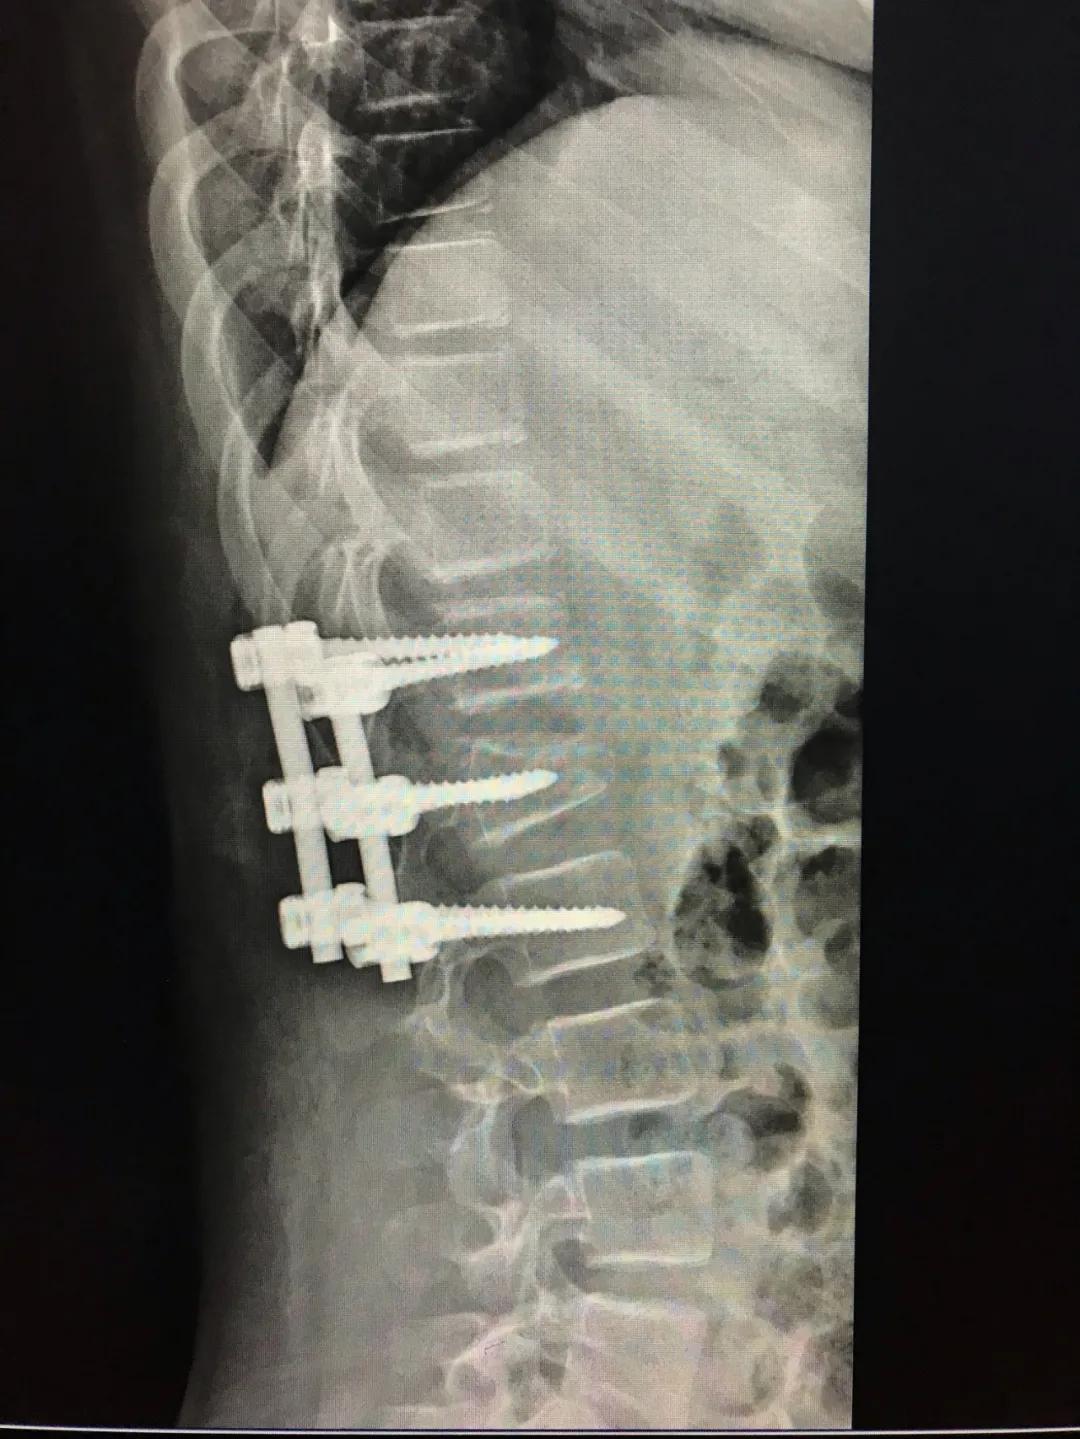

7月27日,高医生带领团队为琪琪做了手术。经过商量,医生决定在琪琪背上打上3根椎弓根钉,用以恢复椎体高度,纠正后凸畸形,支撑骨骼,维持椎体的复位,用微创的方式降低了手术创伤导致的椎旁肌的退变和术后腰背痛的发生率。

“琪琪只有11岁,身体还在发育,对于打钉的要求很高,不能有偏差。”因为年纪小,也增加了手术的难度,高医生说,手术还是非常成功的。

琪琪恢复得也不错,8月1日出院,但腰部的护具还是要戴半个月到一个月才能脱掉。回家之后,日常生活是没有问题的,但不能剧烈运动,至于她脊柱上的根钉,大概要半年后才能取出来了。